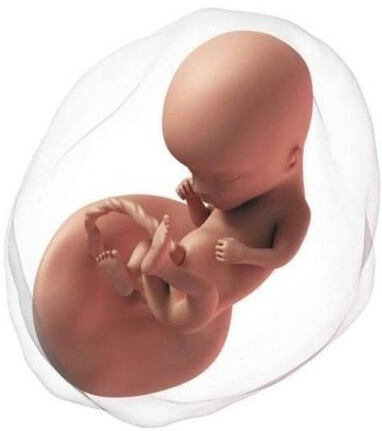

En esta semana inicia el segundo trimestre del embarazo. El feto mide aproximadamente 80 y 95 mm. El bebé crece rápidamente, los brazos alcanzan la proporción adecuada en relación al tamaño del cuerpo. La piel, que ya no es tan "transparente", se cubre aún más por vello denominado lanugo. Los músculos de la cara se desarrollan más, su sistema nervioso está más desarrollado, abre la boca en forma de bostezo, hasta se pueden meter los dedos en la boca. Al abrir la boca entra líquido amniótico, el cual pasa al estómago y los intestinos, lo cual permite que estos crezcan y se desarrollen.

Tu abdomen empieza a crecer, se pierde tu cintura y se produce un aumento progresivo de peso.